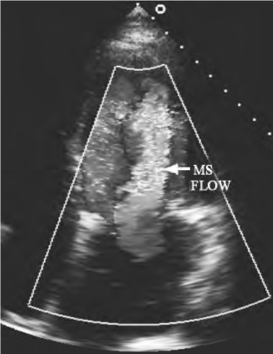

1.17.1第一节 二尖瓣疾病

1.17.1.1一、二尖瓣狭窄